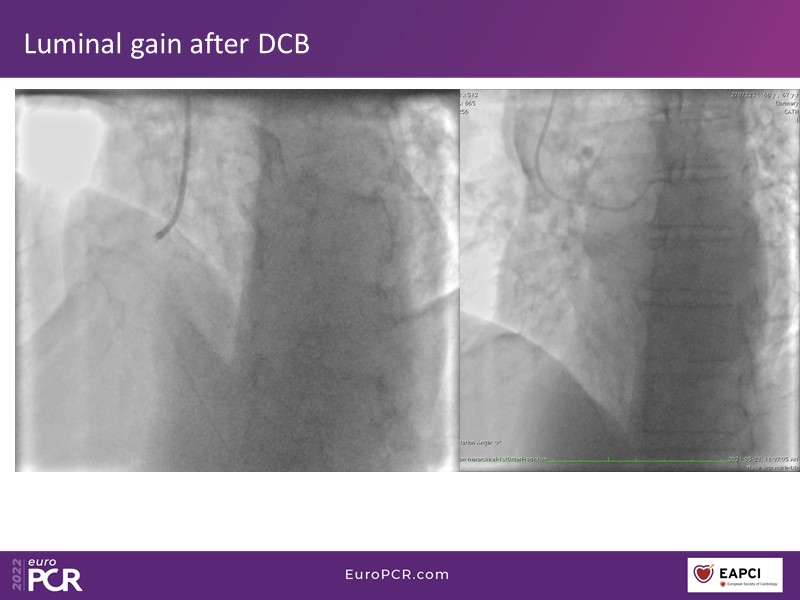

Thanks to the different interventions of this EuroPCR 2022 session, understand the role of paclitaxel DCB in modern era interventional cardiology, the differences, and advantages versus DES, the role of blended therapies in CLS, and learn how to correctly prepare the lesion and obtain the best from this technology on the long term.